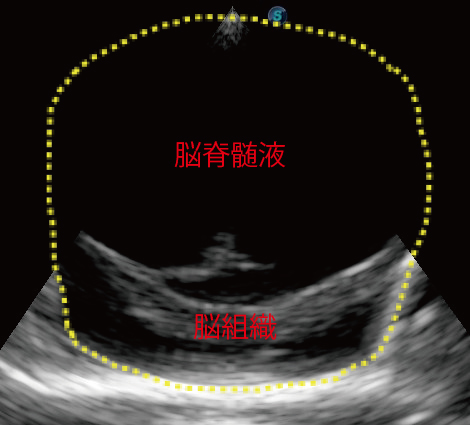

- 頭部超音波検査:過剰に溜まった脳脊髄液を描出することができる場合もあります。

(頭部超音波画像:脳室内に脳脊髄液が大量に溜まり、脳の神経が存在する部分がほとんどみえなくなっています。黄色い点線の内側が頭蓋骨の中、黒い部分が脳脊髄液、灰色の部分が脳組織です。)